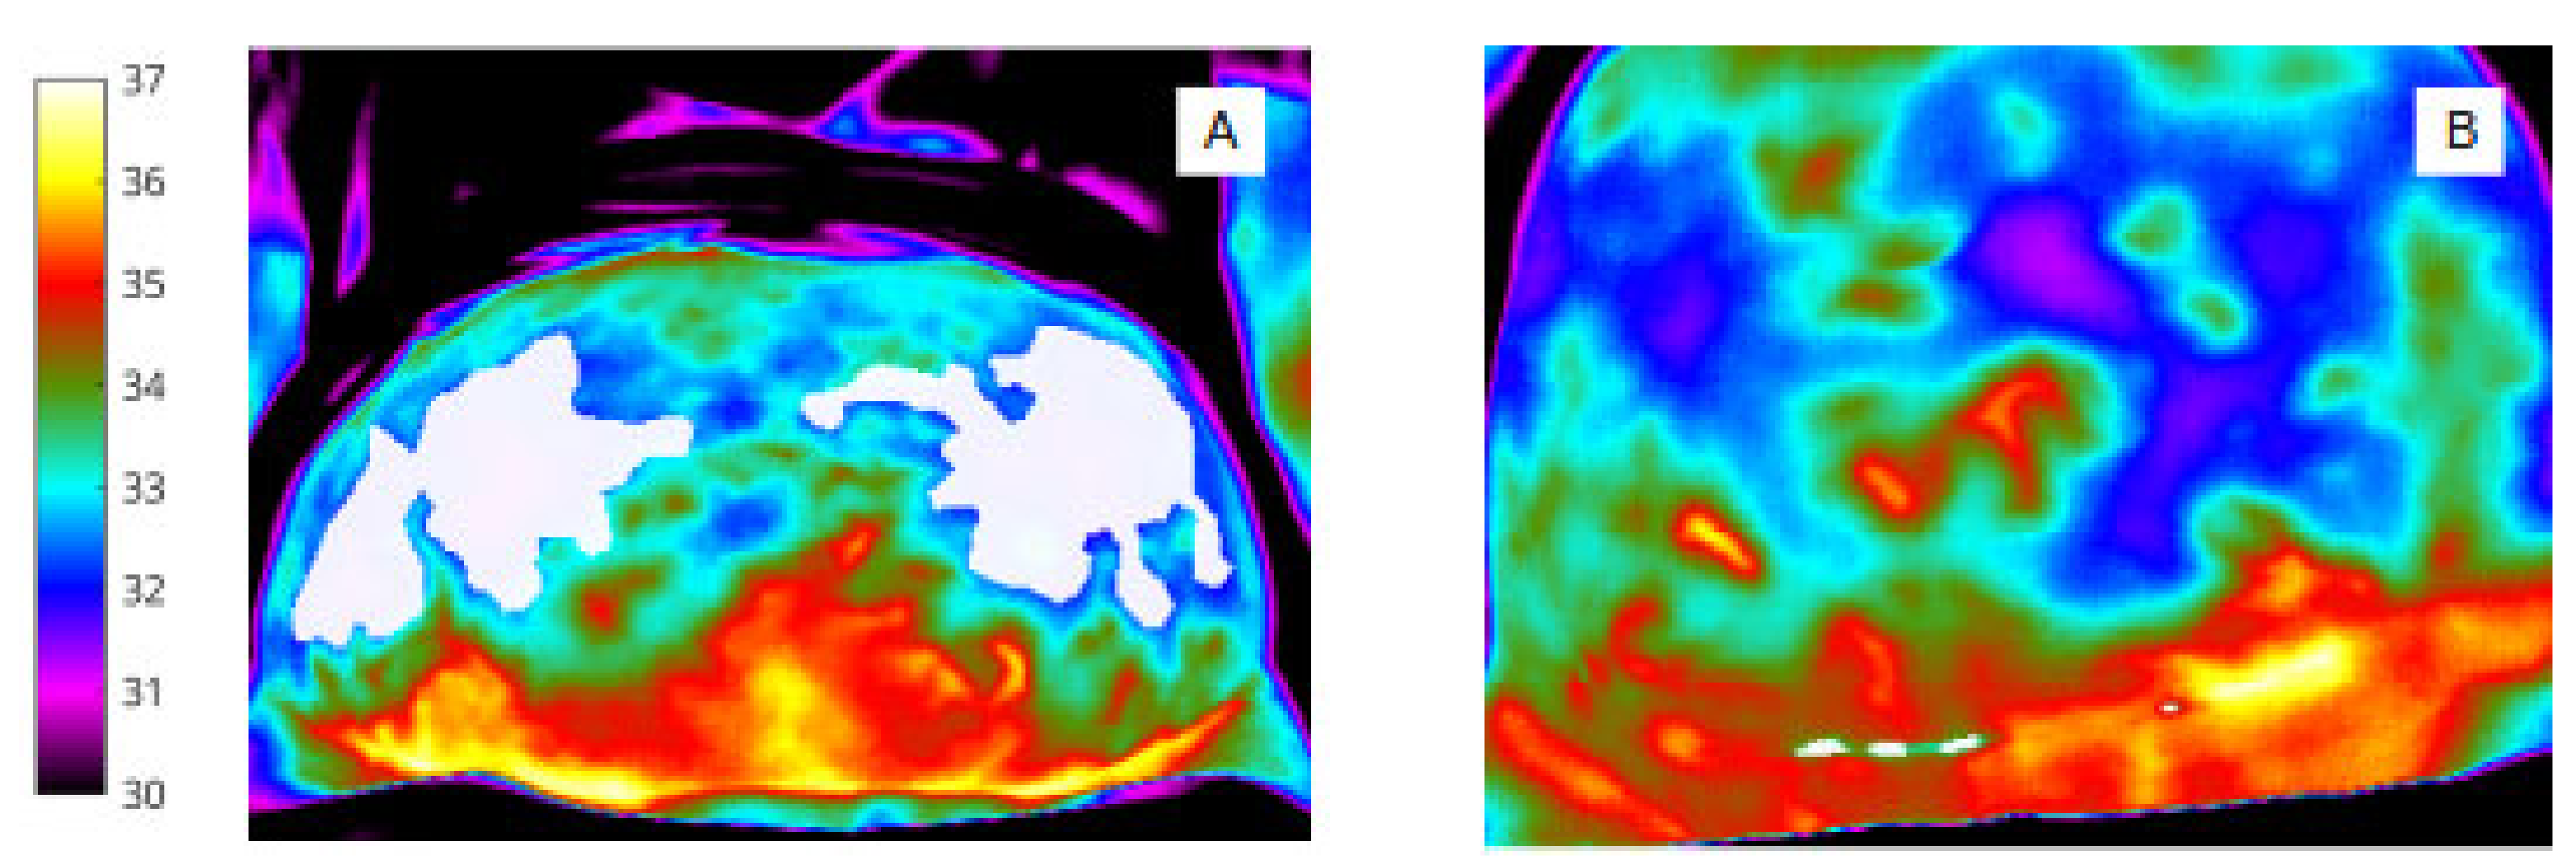

For abdomen (Figure 2A,B) and wound segmentation (Figure 3A,B), the respective regions were identified in infrared and the ROI was selected and cropped. With respect to the surgical site, ROI 2, determining the extent of the area, was often difficult to identify in infrared due to lack of clear anatomical landmarks. To help discern wound area from surrounding healthy skin, reference was made to the corresponding digital image.

Figure 3.

(A) Pixel-based wound segmentation (ROI 2). (B) Binary mask of wound region (ROI 2).